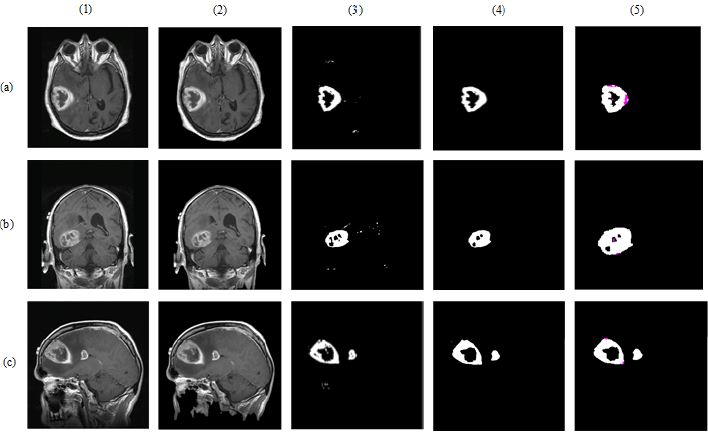

In Eq. (3), to (5), TP refers the correct location of tumor pixels, TN refers to non-tumor pixels. FP refers the perception of healthy pixels as tumor tissue pixels. FN refers the undetected tumor pixels. In Eq. 6, Jsim parameter gives Jaccard’s index of similarity. It takes values between [0, 1]. If the images are completely similar, Jsim parameter is equal to 1. If there is no similarity between the images, the parameter becomes 0. The results of each process performed during brain tumor detection were indicated in Figure 3. In the first column, brain MR images, in the second column, images as a result of pre-processing, in the third column, images formed as a result of thresholding, in the fourth column, images as a result of morphological operations and masking, in the fifth column, images based on the result of Jaccard’s similarity are included and the pink parts in the images show that there is a missing area when compared to actual binary tumor images and the green parts show that there is much area. Rows represent brain MR images of RIDER, Figshare, and REMBREDANT data sets, respectively. When the Figure 3 is reviewed visually, it is seen that tumor regions have been successfully segmented close to real. When the tumor detection results of the data sets were examined, the tumor performance was on the acceptable level for three data sets. It was seen that the best success in tumor detection was obtained from RIDER data set.

The results given in Table 8 confirm the visual evaluation. While rows indicate the names of the data sets, columns present the calculated numerical performance criteria in Table 8. As seen from Table 8, the values of accuracy, sensitivity, specificity and Jaccard’s index calculated for RIDER data set were 98.91%, 98.15%, 98.20%, 98.52% respectively, while these values were 97.44%, 97.12%, 97.54%, 96.88% for Figshare data set and 97.90%, 96.53%, 97.19% and 97.23% for REMBREDANT data set.